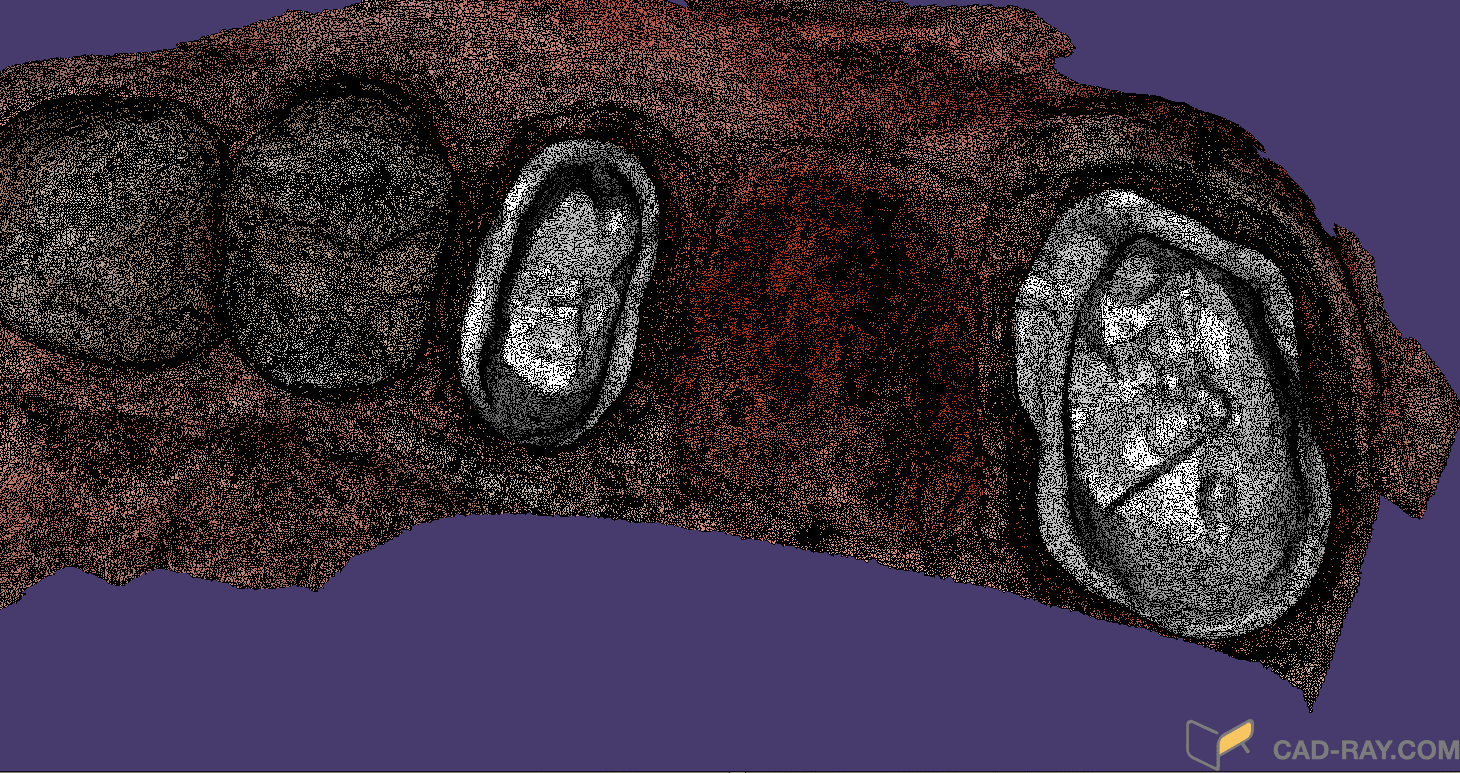

Bridge Replacement with the Medit i500 Using Copy Mode of the Pre-op, White Light for Red Tissue, Blue Light for Tooth Structure, and Segmented Model Building

February 4, 2019This failing three unit fixed partial denture was replaced with the Medit i500 and the CAD-Ray Design Software. While the patient was getting numb, a physical quadrant impression was made […]